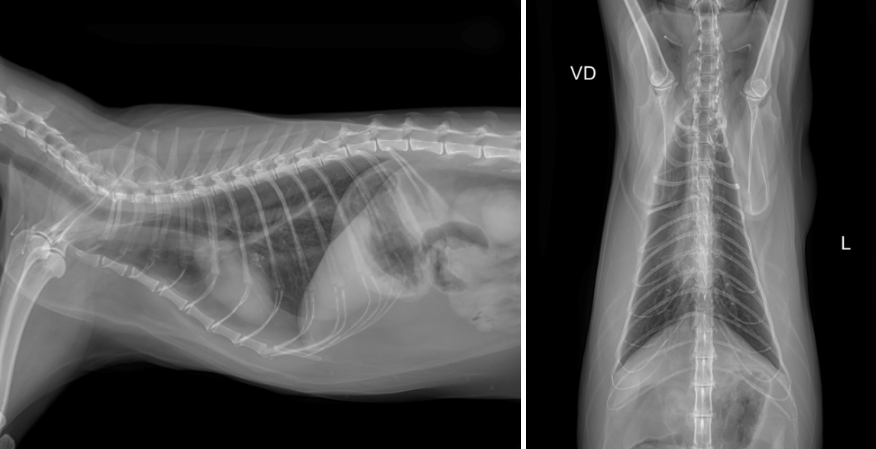

x-ray 검사상 특이소견은 확인되지 않았습니다.

양측 신장의 퇴행성 변화 관찰되며, 신우확장 및 비뇨기 폐색 소견은 확인되지 않았습니다.